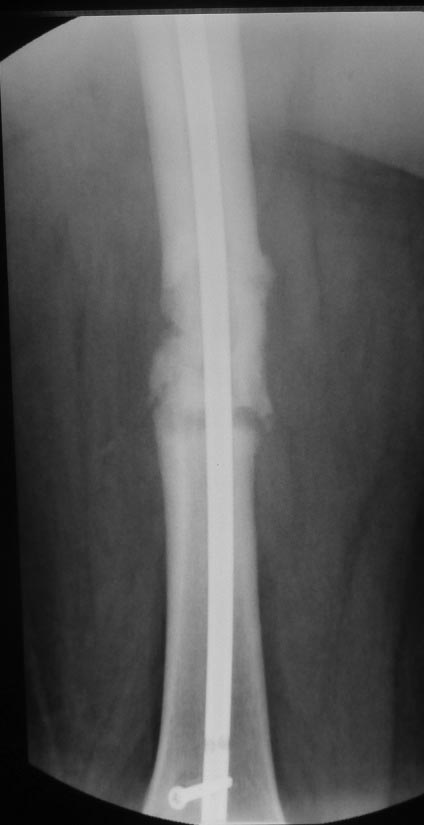

Уважаемые коллеги. Хотелось бы выслушать мнения и советы по представленному случаю. Пациент 42 лет, вес 130 кг, рост около 160 см, сахарный диабет в легкой форме (впервые выявлен после травмы). Травма в феврале 2011 г. - упал с мотоцикла на отдыхе за рубежом. По возвращении в Россию был прооперирован в несколько этапов: в марте 2011 г. - остеосинтез обеих костей правого предплечья пластинами по поводу открытого перелома; интрамедуллярный остеосинтез правого бедра; остеосинтез проксимального конца правой большеберцовой кости. В апреле 2011 г. был доставлен 1 блокирующий винт в дистальное отверстие гвоздя и выполнена пластика крестообразных и наружной боковой связок левого коленного сустава. В феврале 2012 г. были удалены фиксаторы с проксимального конца правой большеберцовой кости и выполнена пластика крестообразных и наружной боковой связок правого коленного сустава. За это время пациент смог начать ходить, сначала с костылями, а затем - без дополнительной опоры. Летом 2013 г. решил укрепить ноги с помощью подъемов пешком на пятый этаж. В результате - усталостная рефрактура правого бедра и перелом интрамедуллярного гвоздя. 09.09.2013 - реостеосинтез латеральным бедренным гвоздем с пластикой костной аутостружкой + СhronoS. Сейчас, через 6 мес после операции, может ходить без дополнительной опоры, периодически беспокоит болезненность в области правого бедра. На сегодняшних КТ - отсутствие признаков консолидации. Нужно ли что то делать и, если да, то что? Рассматриваемые варианты: повторная костная пластика дефекта; доставить блокирующие винты (самый проксимальный винт был удален через 3 мес после операции). Еще раз менять гвоздь не хотелось бы. На представленных снимках: бедро в 2011 г., через несколько мес после операции; в 2012 г., на стадии консолидации; со сломанным гвоздем; сразу после повторной операции (3 рентгенограммы). Все КТ - сегодняшние. Заранее спасибо за ответы.

А какой диаметр последнего стержня? По представленным снимкам кажется, что тонковат...?

Второй гвоздь был на 2 см длиннее и на 1 номер толще предыдущего. По-моему десятка.В принципе какая разница? Впечатление о том, что тонковат, ведь не зависит от реальной толщины гвоздя. Канал не рассверливал. Но забивал с трудом.

Мне тоже показалось, что тонковат. Но, раз операция нежелательна, надо ждать и лечить консервативно. При неуспехе - на мой взгляд, замена стержня на более толстый с рассверливанием канала и, возможно, костной пластикой.

ждать-не ждать? Срочности нет, подождать можно, но активно, т.е. оценить клиническую и рентгенологическую динамику: два месяца назад, сейчас и еще через пару месяцев. Уменьшатся боли, появится более убедительная мозоль - ждите и наблюдайте дальше. Отсутствие положительной динамики можно приравнять к отрицательной динамике. Очевидно, что здесь имеют место быть обе проблемы: биологическая -мозоль слабая и механическая - тонкий гвоздь, недостаточная стабильность. Тогда -удаление, рассверливание (очень аккуратное, по 0.5 мм шаг, острыми фрезами, чтобы не пожечь кость - кортикал толстый и довольно прочный). Для 130 кг диаметр гвоздя минимум 12 мм, лучше больше. Здесь можно и 14мм гвоздь взять и блокировать дистально винтами 6,0 мм. Открывать перелом и пытаться делать еще пластику экстрамедуллярно не стоит. Рассверливания будет достаточно.

Согласен, стержень тонковат в дистальном отломке. Если совсем никак не возможно перепровести с рассверливанием более толстый стержень, можно согласиться с вашим предложением ввести еще один винт в дистальный конец гвоздя, но полностью убрать винты из проксимального отломка, чтобы перенести осевую нагрузку на кость и не опасаться перелома гвоздя или винтов.

Насколько это эффективно в отношении консолидации будет видно примерно через 6 недель. Незабудьте сделать, если его нет, обычный свежий снимок до динамизации для последующего сравнения.